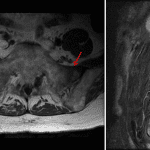

- Linear areas of T1 signal hypointensity and surrounding STIR signal hyperintensity in the bilateral sacral ala

- Sacral insufficiency fractures

Findings consistent with bilateral sacral insufficiency fractures.